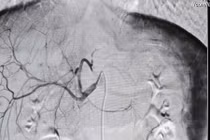

Bệnh viện Quảng Ninh thành công trong việc xử lý vỡ gan độ IV bằng phương pháp can thiệp mạch, giúp bệnh nhân hồi phục tốt, tránh phẫu thuật mở.